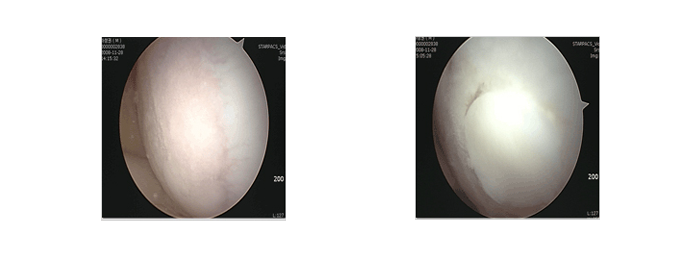

관절경 수술 - 사진

연골 손상

초기 손상은 단순 X-ray에서 발견되기 어려우며 MRI 로 진단할 수 있습니다. 하지만 MRI 도 정확한 병변의 크기나 손상된 연골과 주변의 싱싱한 연골과의 경계등 정확한 정보를 얻기에 부족한 부분이 있을 수 있습니다. 최종적인 상태 파악은 관절경으로 하게 되며 MRI 등으로 병변이 확인된 경우 수술 준비를 모두 갖추고 관절경을 하게 됩니다.